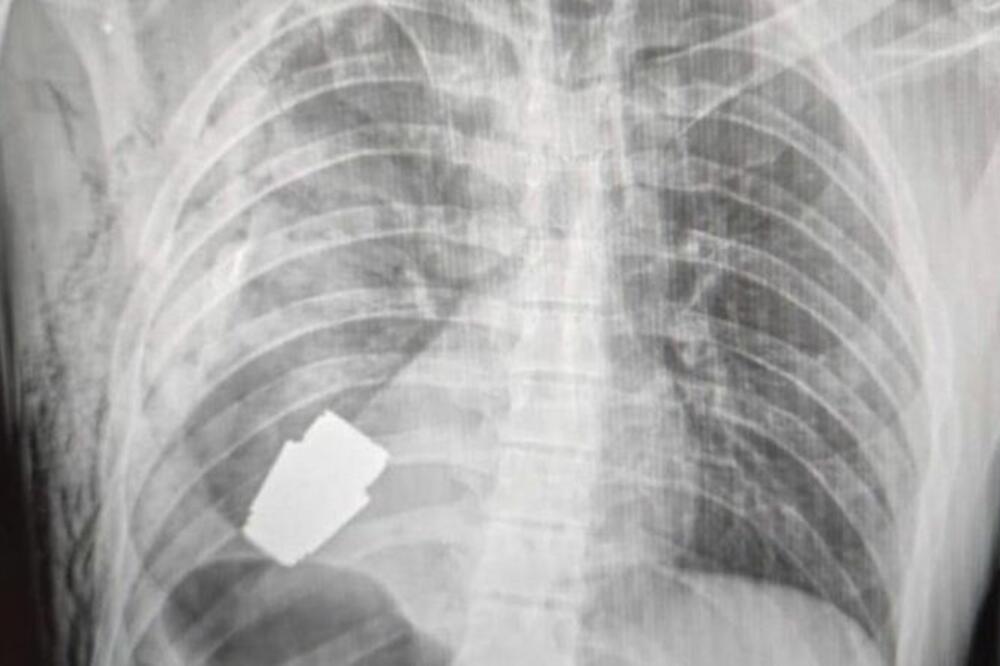

Rendgen pokazuje da je granata blizu srca vojnika, Foto: Facebook/Ukraine medical force command

Na fotografija pre i posle na Fejsbuk stranici medicinske službe ukrajinskih oružanih snaga vidi se rendgenski snimak eksploziva blizu srca vojnika, dok na drugoj slici hirurg drži krvavu napravu.

Dodaje se da je uređaj VOG granata - komad municije dužine četiri centimetara koji se ispaljuje iz bacača granata i može da putuje oko 400 metara, a napravljen je tako da eksplodira tik iznad zemlje.